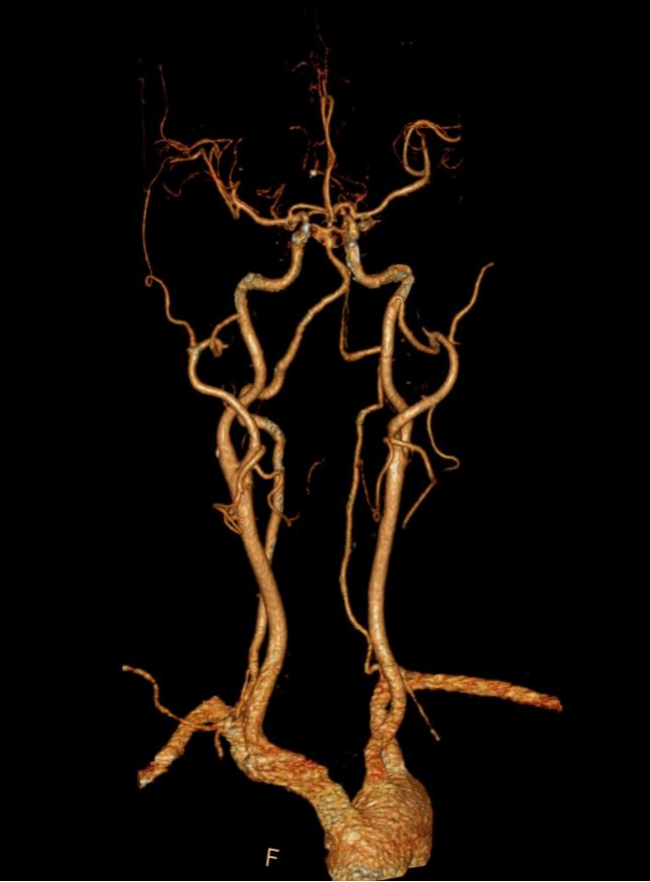

全身各部位血管造影:Incisive CT可以轻松实现大范围CT血管造影(CTA),准确了解血管及相关脏器的形态结构,评估血管及脏器功能,准确判断出血,栓塞、血管瘤、血管畸形、狭窄及肿瘤供血情况,为临床治疗提供极大帮助。

▲ 头颈部CTA、硬化斑块清晰显示